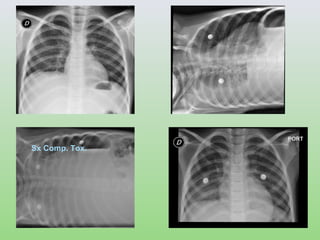

ESTUDIOS RADIOLOGICOS

Sx Comp. Tox.

Journal of Tropical Pediatrics Vol. 48 December